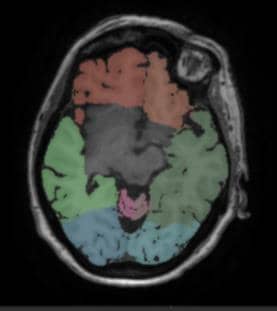

Automatic segmentation for different areas of the brain

Leveraging a 3D T1-weighted scan, volumes of total brain, brain lobes (frontal, temporal, parietal and occipital), cerebellum and hippocampus are computed using state-of-the-art automatic segmentation techniques. These volumes can be compared to the reference values based on a healthy population study, or to a follow-up exam as described later.